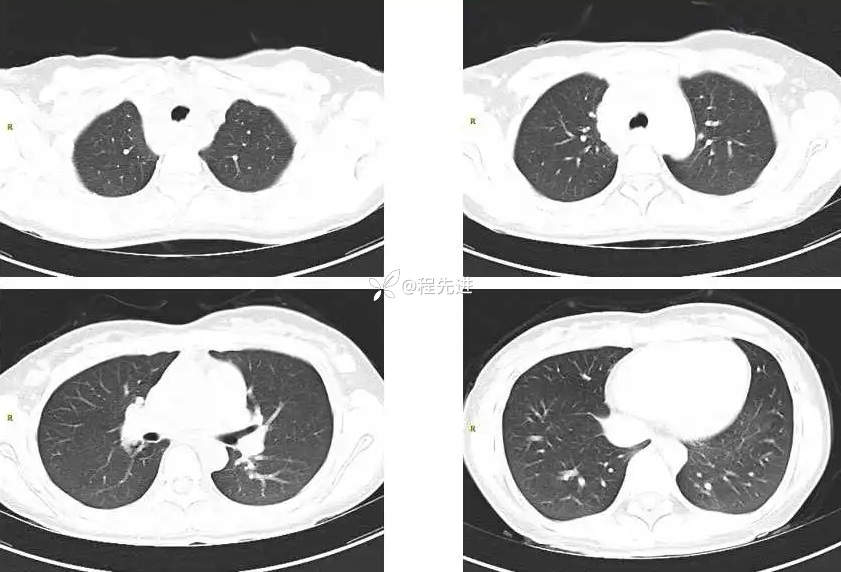

CT平扫+增强: